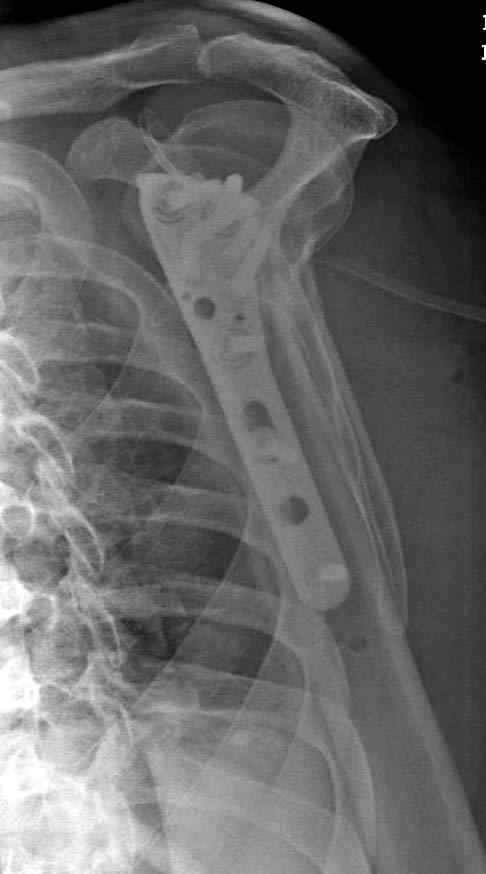

Пациентка Б.1953 г.р., врач-терапевт. Травма 27.11.08г. Падение с высоты роста. Выявлен закрытый не осложненный оскольчатый перелом хирургической шейки левого плеча со смещением. 02.12.08г. оперирована. Выполнена открытая репозиция и остеосинтез пластиной LCP Деост с дополнительной фиксацией отдельно лежащего фрагмента винтом. Послеоперационный период протекал без особенностей, заживление раны первичным натяжением. Швы сняты через 10 дней. Иммобилизация левой верхней конечности клиновидной подушкой 4 недели. По окончании срока – рентген-контроль и умеренная разработка плечевого сустава. В течении месяца функция левого плечевого сустава восстановилась удовлетворительно: поднятие руки до 110 гр., отведение - 90 гр. и до 110 гр. отведение с лопаткой. Отведение руки назад – 20 гр. Наружная и внутренняя ротация – 20 гр. Пациентка по настоянию самостоятельно вышла на работу. 27.03.09 при контрольном осмотре жалоб не предъявляет, болевой синдром в левом плечевом суставе отсутствует. Отведение плеча активно до 90 гр, пассивно с лопаткой до 110 гр., поднятие – 110 гр, отведение назад 20 гр, наружная и внутренняя ротация по 20 гр. На контрольных рентгенограммах отмечается смещение металлоконструкции, ротация головки плеча с приведением дистального отломка на 13 гр. и смещением к зади на 30 гр. Рентгенограммы прилагаются. Ваш взгляд на дальнейшую тактику лечения пациентки?

Рентгенограммы действительно с дефектом укладки, но интраоперационная репозиция, можете поверить, была удовлетворительная как в акcиальной, так и в сагиттальной плоскостях. Интраоперационная рентгенограмма прилагается, хотя укладка тоже на ахти. По тактике - разделяю Ваше мнение об отсутствии необходимости реостеосинтеза, а тем более об эндопротезировании, хотя это все было предложено пациентке ведущими ортопедами-травматологами России.

Здесь пример открытой репозиции 57 летнего с переломом плеча (1,2) смещение обнаружено на интероперационном снимке. При нормальной прямой проекция (3) угловое смещение обнаружили в аксиальной проекции (4)

После устранения смещения пластина установлена выше (5,6,7) и финальные снимки (8,9,10)